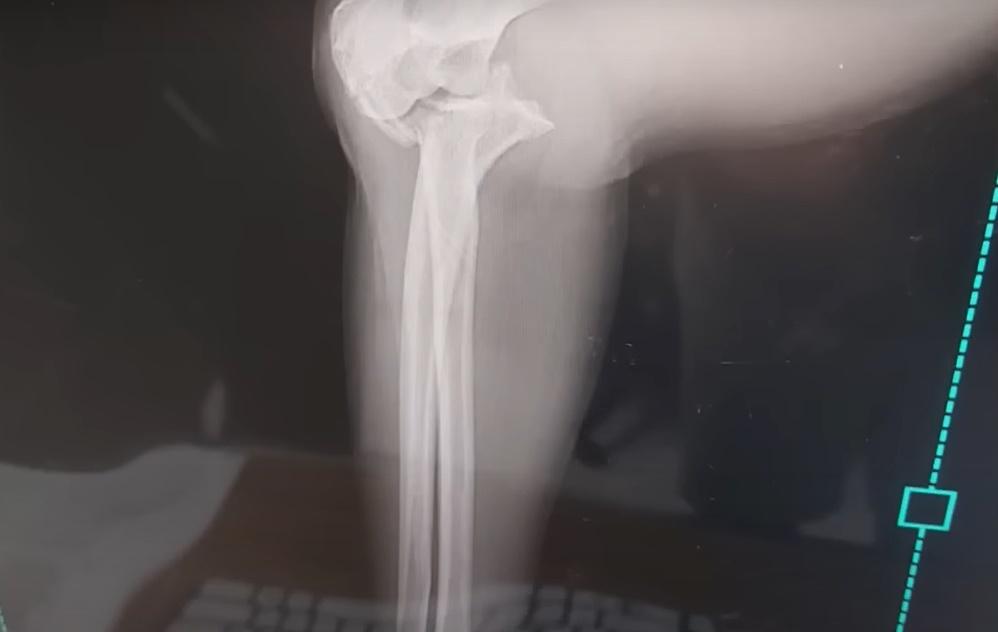

事後Beth被帶到酒店的前台敷冰,由於傷口不斷腫脹,便被送到醫院檢查,透過X光機發現她的手臂骨折,隨即要接受手術,以鋼板和骨釘螺絲固定骨頭。Beth又提到,園方原先承諾支付一半的醫療費用,不過後來不再回應夫婦的聯絡,直到外國傳媒報道事件,最近終於收到園方的賠償。Beth與丈夫沒有將這個意外歸咎於大象,但勸誡其他遊客到峇里島接觸大象時要注意風險。Beth提醒:「這將是一條漫長的康復之路。」